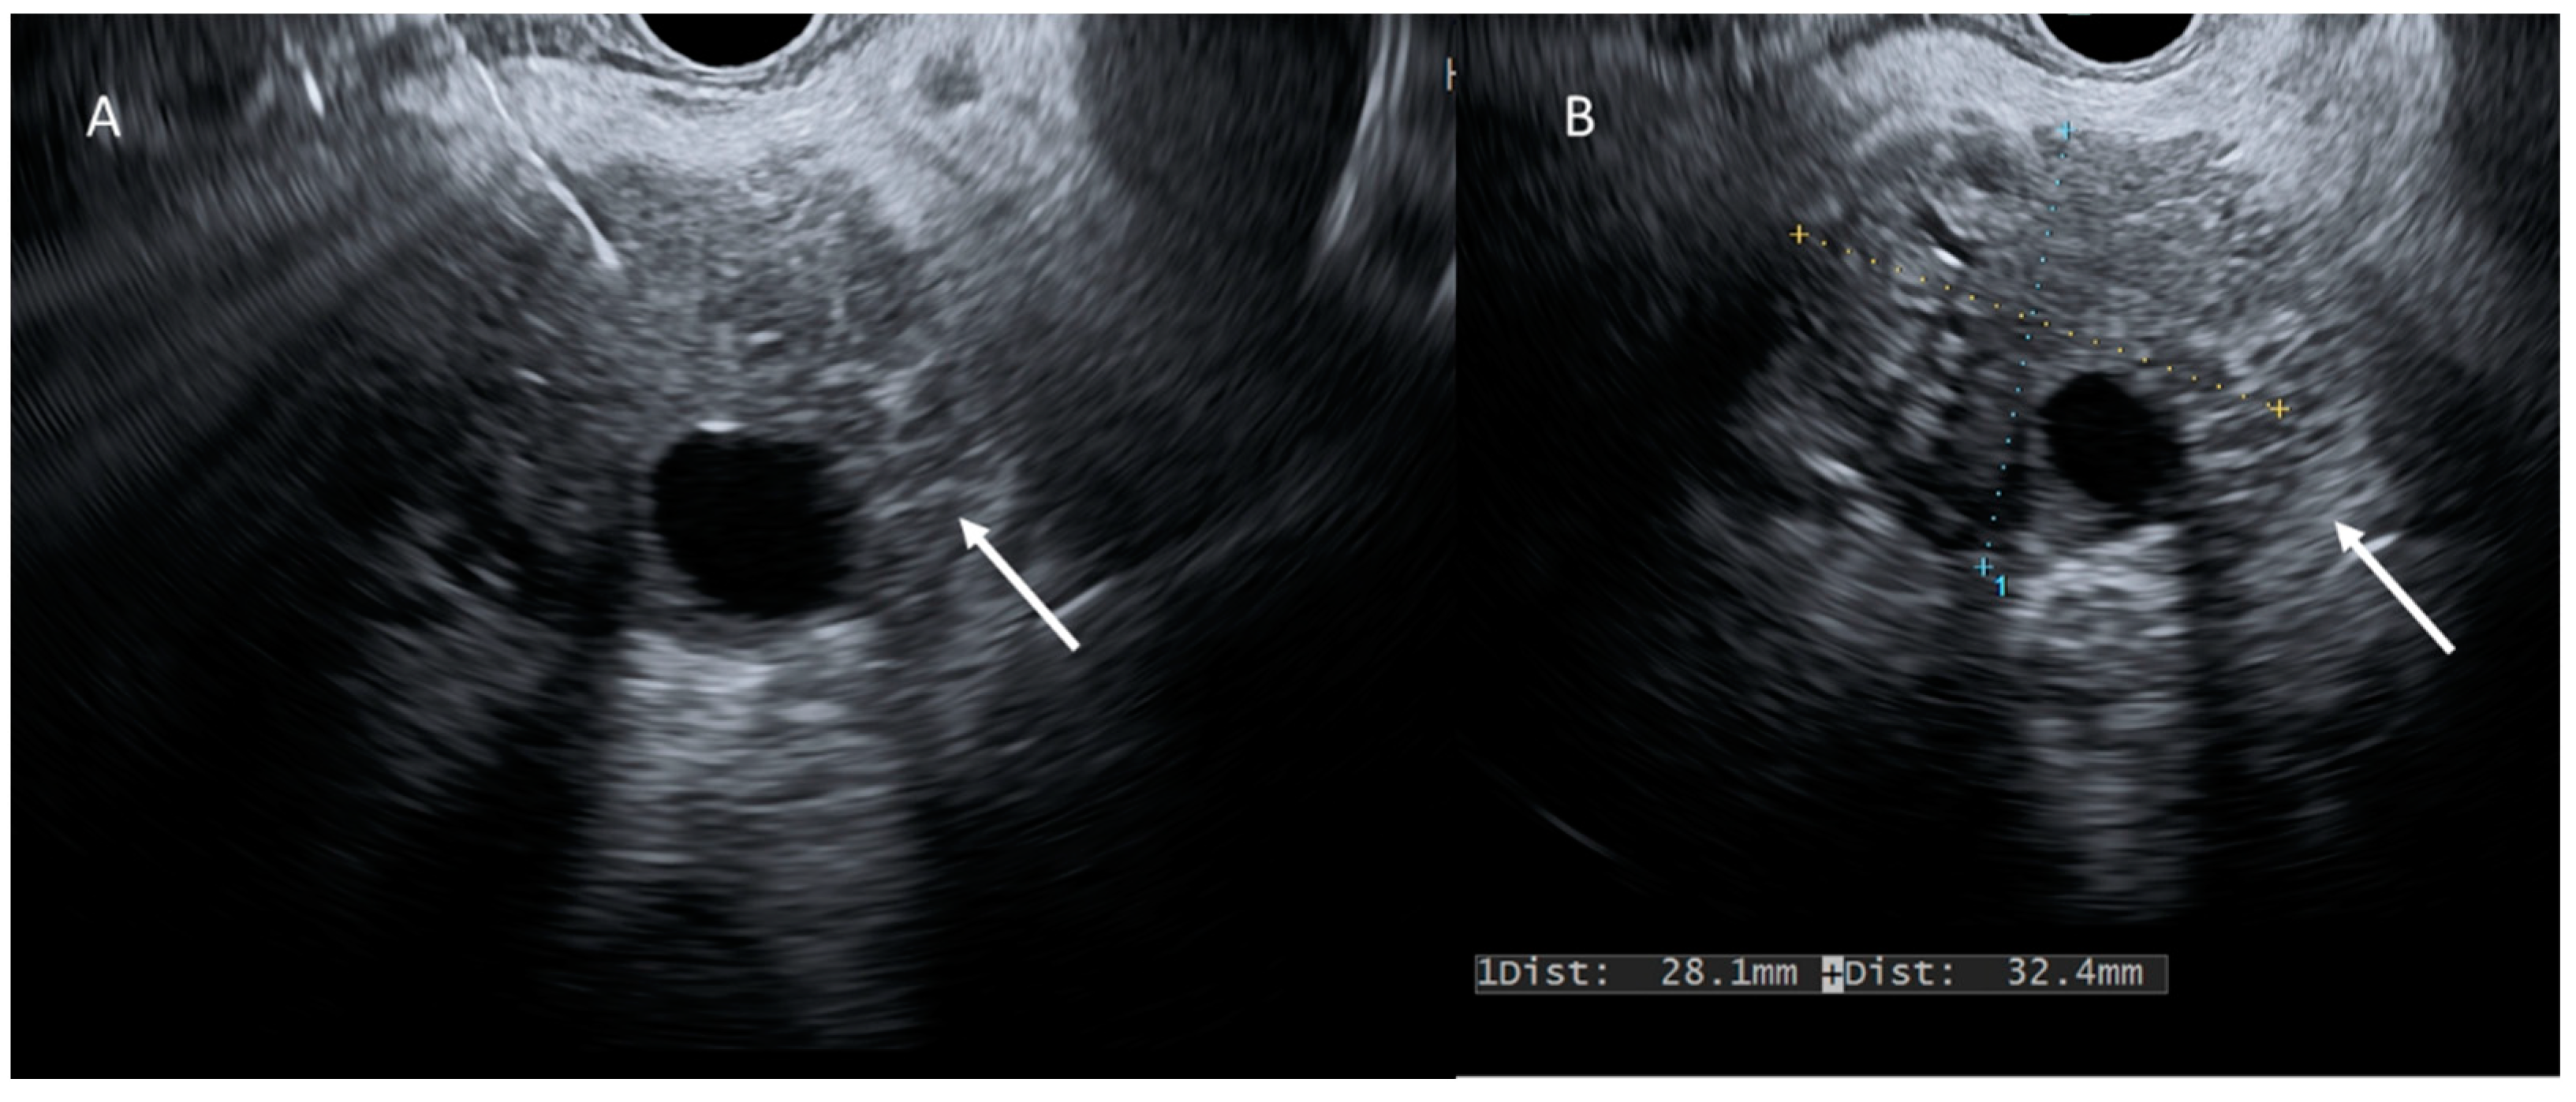

- Kitano, M.; Yoshida, T.; Itonaga, M.; Tamura, T.; Hatamaru, K.; Yamashita, Y. Impact of endoscopic ultrasonography on diagnosis of pancreatic cancer. J. Gastroenterol. 2018, 54, 19–32. [Google Scholar] [CrossRef] [PubMed]

- Jang, D.K.; Song, B.J.; Ryu, J.K.; Chung, K.H.; Lee, B.S.; Park, J.K.; Lee, S.H.; Kim, Y.T.; Lee, J.Y. Preoperative diagnosis of pancreatic cystic lesions: The accuracy of endoscopic ultrasound and cross-sectional imaging. Pancreas 2015, 44, 1329–1333. [Google Scholar] [CrossRef]